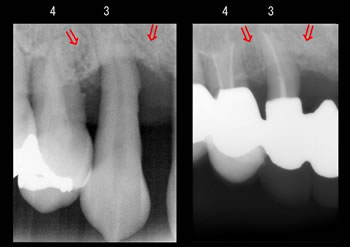

お口の中の同じ部位で「左が初診時」で「右が再生治療後」のレントゲンです! |

赤い矢印の部分が歯槽骨の再生した場所です。

(3は3番目の歯、4は4番目の歯です) |

10年経過しておりますが、定期的にメンテナンスに来られており今でも歯肉の状態は安定しており問題ありません! |